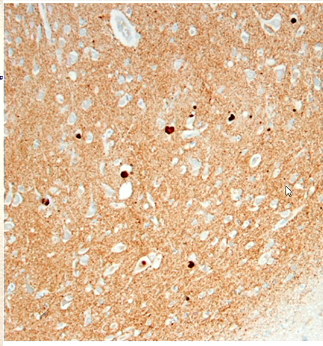

What are we looking at?

beta amyloid immunostain